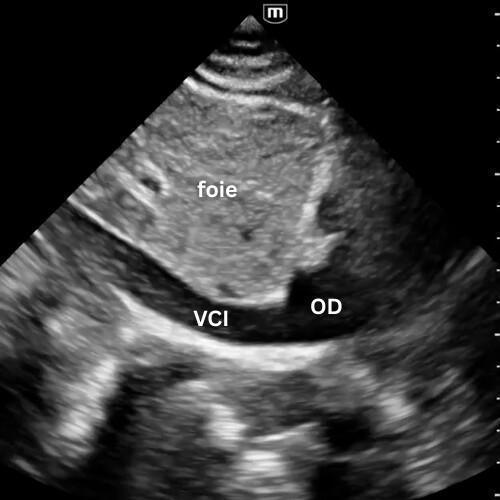

🔹 Vue Sous-costale (subxiphoïdienne)

→ Le cœur bouge-t-il ? y a-t-il du liquide ?

Placer la sonde sous l’appendice xiphoïde, dirigée vers l’épaule gauche, en s’aidant du foie comme amplificateur acoustique.

C’est la fenêtre universelle de la réanimation, utilisable pendant la RCP.

Elle permet de visualiser les quatre cavités, de détecter un épanchement péricardique même discret, et d’apprécier grossièrement la fonction myocardique.

Un simple regard suffit à trancher entre activité cardiaque présente ou asystolie réelle.

🔹 Veine Cave Inférieure (VCI)

→ Le patient est-il plein ou vide ?

Depuis la fenêtre sous-xiphoïdienne, faites pivoter la sonde en orientant le marqueur vers la tête du patient, légèrement vers son épaule gauche, afin de visualiser la veine cave inférieure à son abouchement dans l’oreillette droite.

Sa taille et sa variabilité respiratoire donnent une idée du remplissage, mais cette approche devient moins fiable devant les autres mesures comme l'evaluation des pressions de remplissage du VG. Ces techniques seront détaillées dans la suite du module cardiaque.

La VCI peut encore dépanner, mais ne doit plus être la boussole du remplissage toute seule.